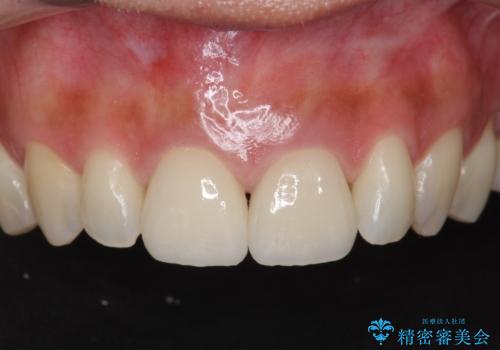

![[深い虫歯] 根管治療・歯周外科治療を行い歯を保存するの症例 治療後](https://seimitsushinbi.jp/wp/wp-content/uploads/2019/10/f94f918301554464d21b1fb7c0a3d93b-500x350.jpg?v=1572444693)